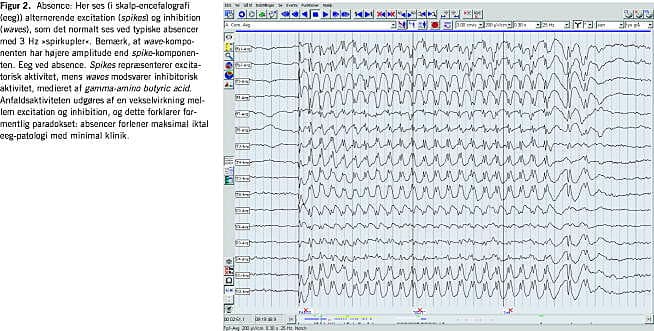

• Absencer: »excitations-inhibitions-kobling«, hvor impulsudsendelsen alternerer med massiv regional inhibition, formidlet via gamma-amino butyric acid (GABA)-aktivitet (Figur 2 ). Denne mekanisme, der altså er meget forskellig fra den foregående, ses typisk ved absencer. Dette forklarer, at denne anfaldstype som regel ikke reagerer på en del af de antiepileptika, der generelt ellers er særdeles effektive (f.eks. carbamazepin/oxcarbazepin), og at stoffer, der forstærker GABA-aktiviteten i nervesystemet (vigabatrin og tiagabin), oftest vil medføre en forværring af anfaldene. Hermed understreges betydningen af at klassificere anfaldene så præcist som muligt. Ved absencer er interiktalt og iktalt eeg kvalitativt identiske.